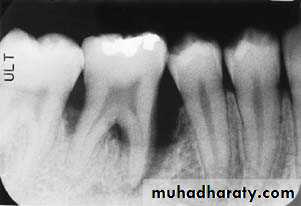

• Severity: classified to

Mild bone loss: crestal changes (The anterior regions show blunting of the alveolar crests and slight loss of alveolar bone height.Posteriorly show loss of the normally sharp angle between the lamina dura and alveolar crest).

• Moderate bone loss: bone loss of 10-33%.

• Severe bone loss: bone loss of 33% or more.

Mild bone loss